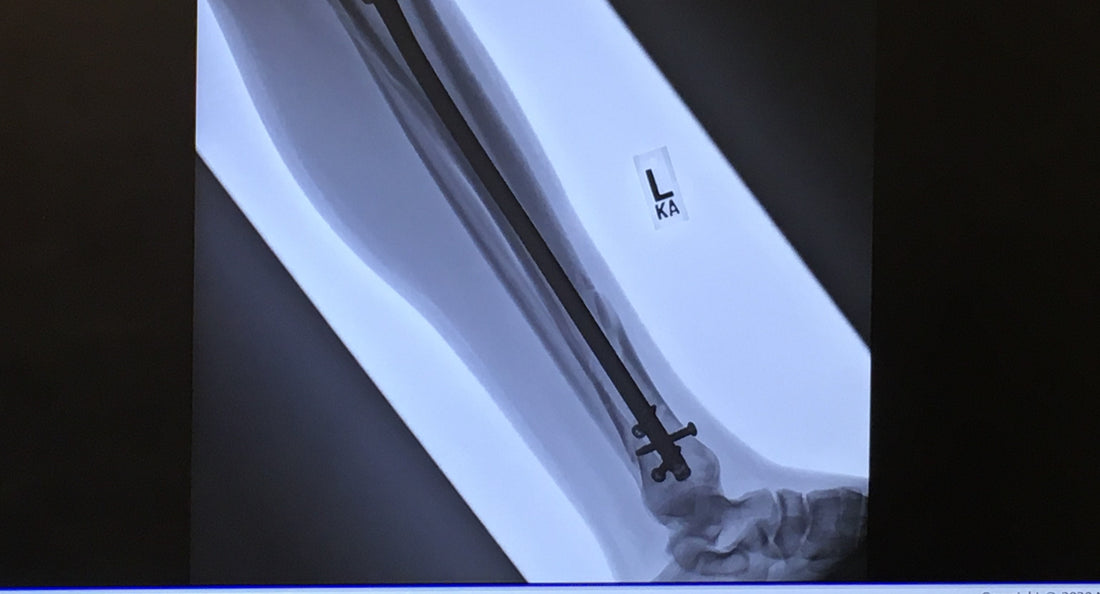

Marr ultimately had to have a metal rod and several pins inserted into the bone. Photo: Mike Marr